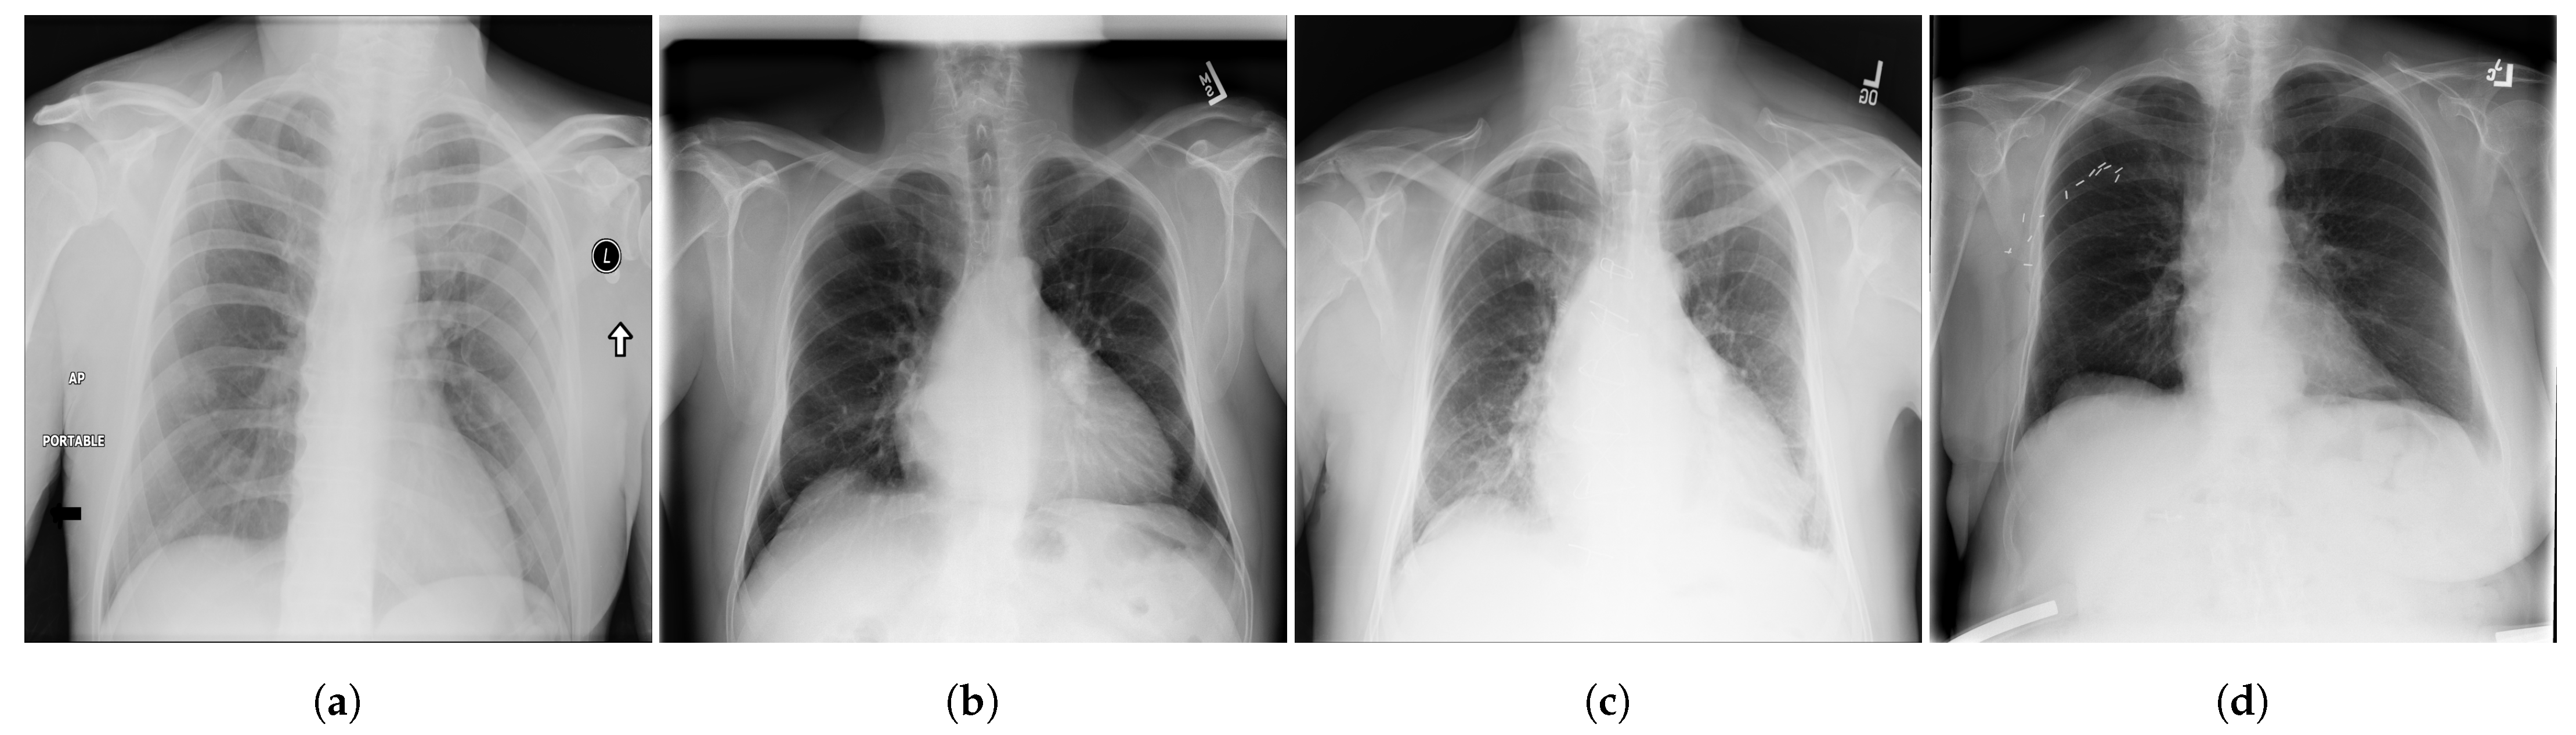

Figure 4.

Examples of CXR images from VinDr-CXR dataset [48] where, (a) Infiltration; (b) Pleural Effusion; (c) Pneumothorax; (d) Pulmonary Fibrosis.